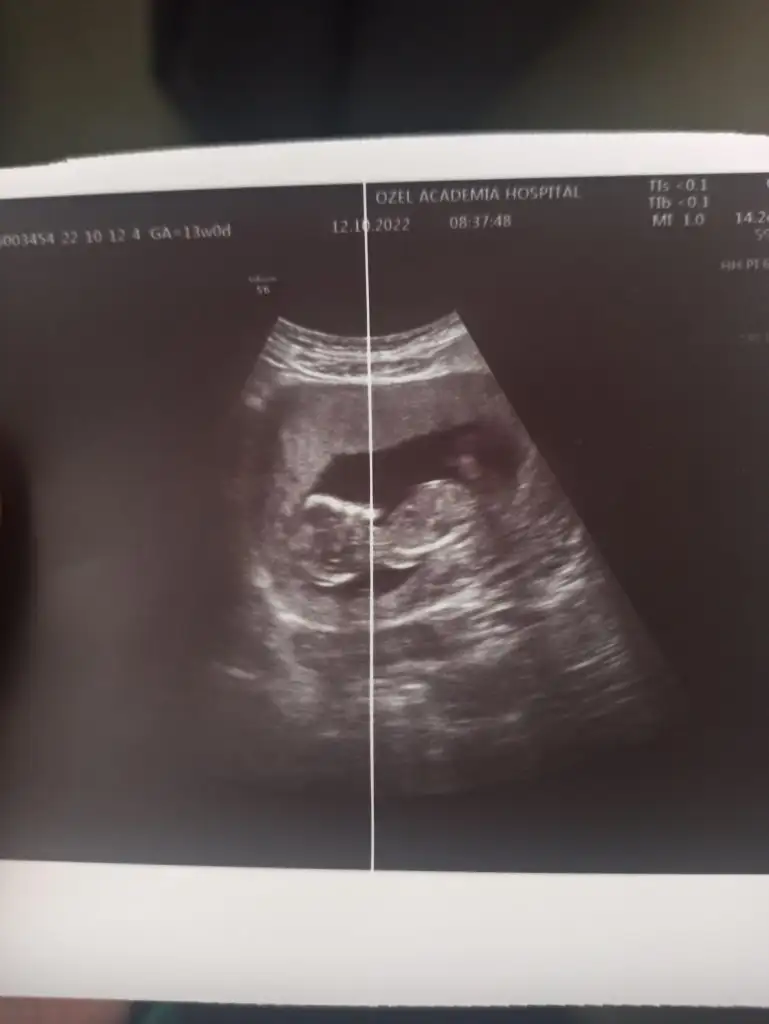

Kizlar kizlarr ben geldim. Kontrolüm vardi ense kalınlığına baktı doktor çok şükür normalmiş. Bı sıkıntı görmedi gelişimi ile ilgili. Bebisim de çok tatlı hareket ediyordu 🥰 cinsiyetle ilgili de bi tahminde bulundu erkeğe benziyor dedi küçük bı çıkıntı gördüm dedi. İlk oğlumda bu haftalarda çok daha net belliydi ben de görmüştüm ama bunu görmedim doktor gördü. Kesin konuşmuyorum bazen bu haftalarda kızlarda da böyle çıkıntı olabiliyor dedi ama ben yine de erkeğe benzettim dedi hayırlısı olsun artık sağlıklı olsun da ♥️

ayy ne güzel, nasıl kesin denildi çok mu net cıktı ultrasonda merak ettm, varsa usg atarmısınız kıyas adına:)

Bebeğimiz ayaklarını üst üste atmıştı 🤭 o yüzden doktorum çok net girebildi